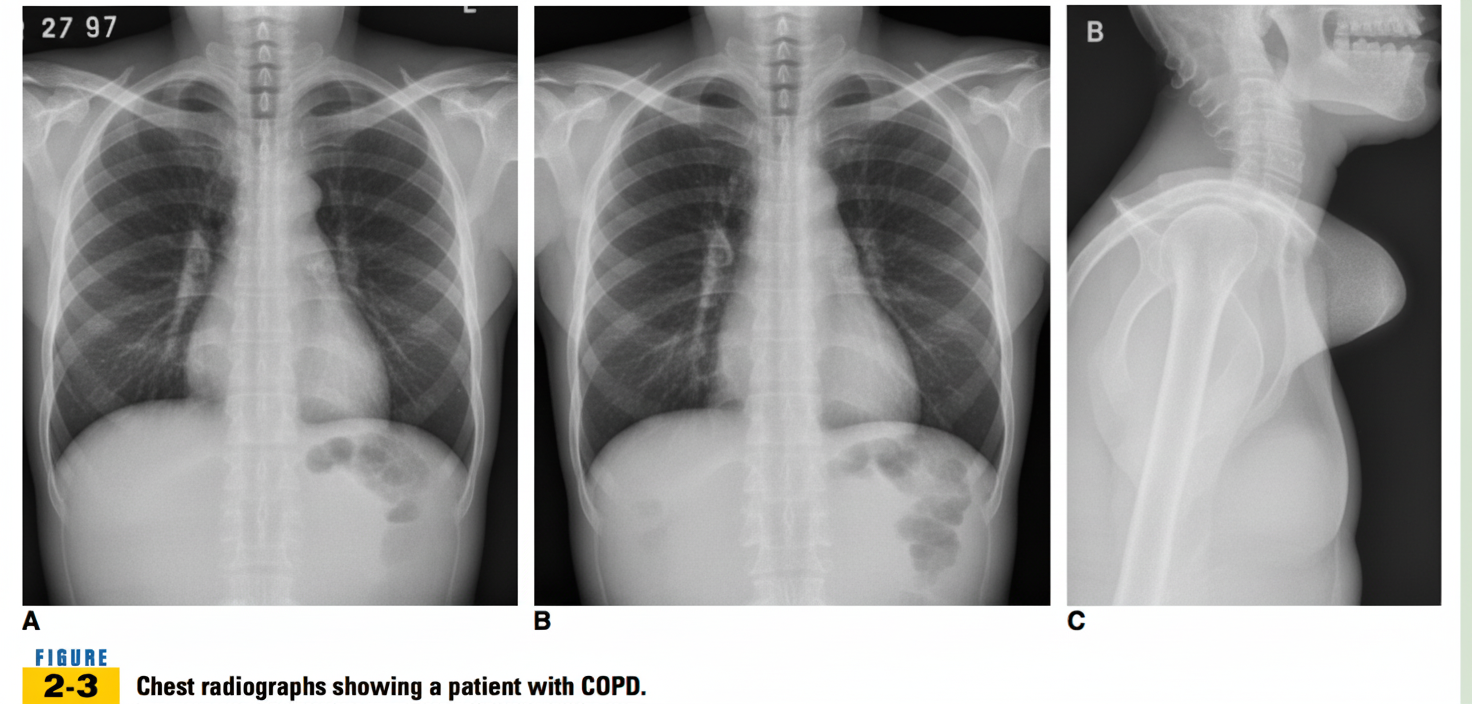

Explanation: ***Emphysema*** - Classic chest X-ray features include **hyperinflation** with **flattened diaphragms**, **barrel chest** appearance, and **hyperlucent lung fields** with **attenuated vascular markings**. - The **increased anteroposterior diameter** and **reduced cardiac silhouette** are characteristic findings in advanced emphysema. *Pneumothorax* - Would show **absent lung markings** in the affected area with a visible **visceral pleural line** separating collapsed lung from pleural space. - Typically presents with **sudden onset chest pain** and **dyspnea**, not the chronic progressive pattern seen in emphysema. *Bronchiectasis* - Characterized by **tramline shadows** (parallel lines representing dilated bronchi) and **ring shadows** (dilated bronchi seen end-on). - Often shows **increased markings** and **honeycombing** rather than the hyperlucent fields typical of emphysema. *Cardiomegaly* - Defined by **cardiothoracic ratio >0.5** with an enlarged cardiac silhouette on chest X-ray. - The heart shadow would be **prominently enlarged**, which contrasts with the **small heart** appearance often seen in emphysema due to hyperinflation.

Chronic Obstructive Pulmonary Disease